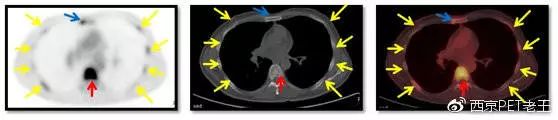

我们又把CT调整到骨窗,看骨骼病变的情况,可以看到全身绝大部分骨骼都有转移,但骨质结构破坏不明显(中列),说明这种是早期的骨转移,如下图:

红色箭头:胸椎及附件转移;黄色:肋骨转移;绿色:肩胛骨转移;蓝色:锁骨胸骨端转移

红色箭头:胸椎转移;黄色:肋骨转移;蓝色:胸骨转移

我们又发现了这么多的骨转移病变,那原发病灶究竟在哪里呢?我们仔细寻找,在左肺上叶发现了一个空洞样病变,边缘见细毛刺及胸膜牵拉征,呈葡萄糖代谢异常增高,我们考虑为恶性病变(肺癌?),如下图:

左肺上叶发现了一个空洞样病变(红色)